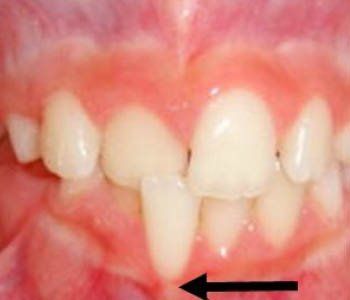

Anterior Crossbite

In the front of the mouth, one or more of the top teeth is stuck behind the bottom teeth.